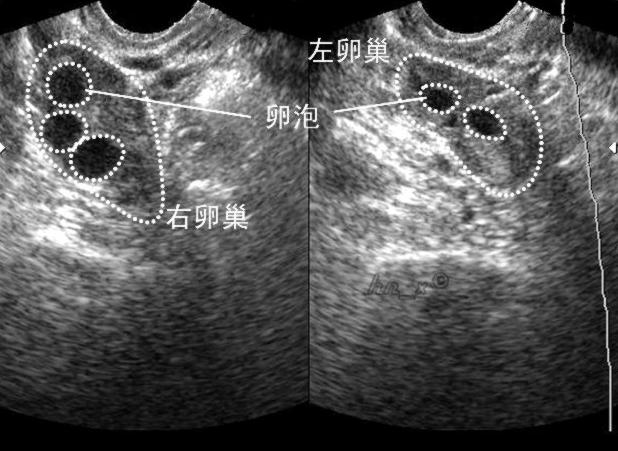

超声卵泡监测就是借助超声仪器,对女性体内的卵泡进行监测,可以分辨2-4mm的卵泡,从月经周期第9天开始,一般1-3天左右观察1次,连续观察可以看到卵泡逐渐长大,向卵巢迁移,第9-12天确定优势卵泡。然后再选取合适的做进一步的治疗措施,或体外受精或体内受精。

B超下的卵泡